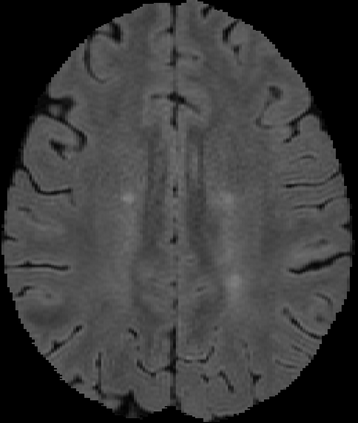

Assessment of lesions and their longitudinal progression from brain magnetic resonance (MR) images plays a crucial role in diagnosing and monitoring multiple sclerosis (MS). Machine learning models have demonstrated a great potential for automated MS lesion segmentation. Training such models typically requires large-scale high-quality datasets that are consistently annotated. However, MS imaging datasets are often small, segregated across multiple sites, with different formats (cross-sectional or longitudinal), and diverse annotation styles. This poses a significant challenge to train a unified MS lesion segmentation model. To tackle this challenge, we present SegHeD, a novel multi-dataset multi-task segmentation model that can incorporate heterogeneous data as input and perform all-lesion, new-lesion, as well as vanishing-lesion segmentation. Furthermore, we account for domain knowledge about MS lesions, incorporating longitudinal, spatial, and volumetric constraints into the segmentation model. SegHeD is assessed on five MS datasets and achieves a high performance in all, new, and vanishing-lesion segmentation, outperforming several state-of-the-art methods in this field.